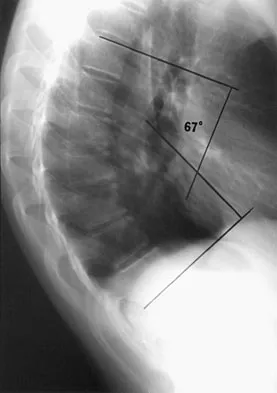

Examination of a 13-year-old boy with asymptomatic poor posture reveals increased thoracic kyphosis that is fairly rigid and accentuates during forward bending. The neurologic examination is normal. Spinal radiographs show 10 degrees of scoliosis at Risser stage 2, and there is no evidence of spondylolisthesis. A standing lateral view of the thoracic spine is shown in Figure 41. The kyphosis corrects to 50 degrees. Management should consist of